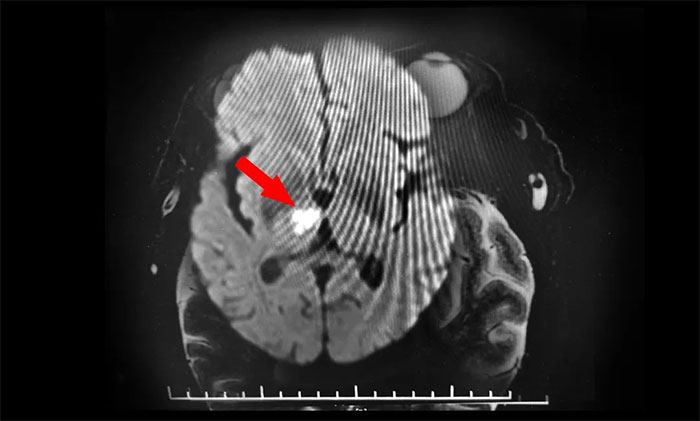

▲ DWI确诊脑干梗死

再次行MR头颅MRI平扫+增强+DWI+MRA,提示脑干、右侧丘脑及双侧大脑半球白质多发梗塞灶及缺血灶(中脑及右侧丘脑梗塞急性期),右侧大脑后动脉狭窄,右MCA-M1段狭窄。至此,该患者双侧动眼神经损伤原因诊断明确,病因为右侧中脑梗死所致,责任血管为右PCA-P1的狭窄致中脑旁正中动脉闭塞,为动眼红核综合征,导致同侧动眼神经麻痹伴对侧肢体共济失调,同时累及右丘脑旁正中动脉。

张静波主任指出,DWI是诊断急性脑梗死的有力武器,但是每个人的脑血管侧支循环不同,DWI没有固定的显影时间,特别是对于后循环的脑梗死,DWI更容易出现阴性,这些都给诊断增加了难度。